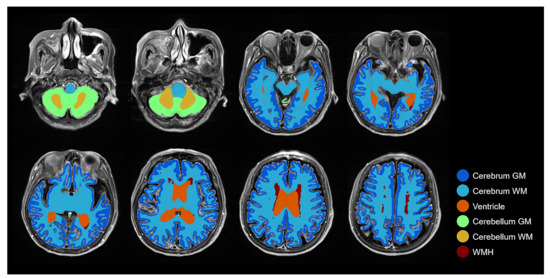

2.2. Overview of the Proposed Method

2.3. Brain Tissue Segmentation from FLAIR MRI: Pseudo-Labeling-Based Segmentation

2.4.1. Deep Learning-Based Initial Segmentation

2.4.2. Morphological Label Correction